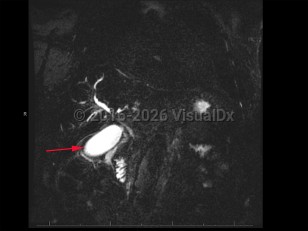

Fibroblast growth factor receptor (FGFR) plays a role in driving the disease, and inhibitors of that growth factor are under study.

Overall prognosis is poor, as many patients present with advanced disease. Early detection of tumors that can be resected surgically portends the most favorable prognosis. Chemotherapy can slow disease progression but is rarely curative.